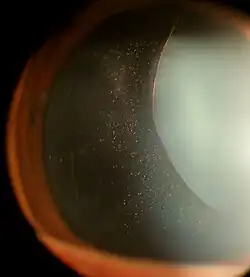

The zonules of Zinn are difficult to visualize using a slit lamp, but may be seen with exceptional dilation of the pupil, or if a coloboma of the iris or a subluxation of the lens is present.[8] The number of zonules present in a person appears to decrease with age.[5] The zonules insert around the outer margin of the lens (equator), both anteriorly and posteriorly.[9]